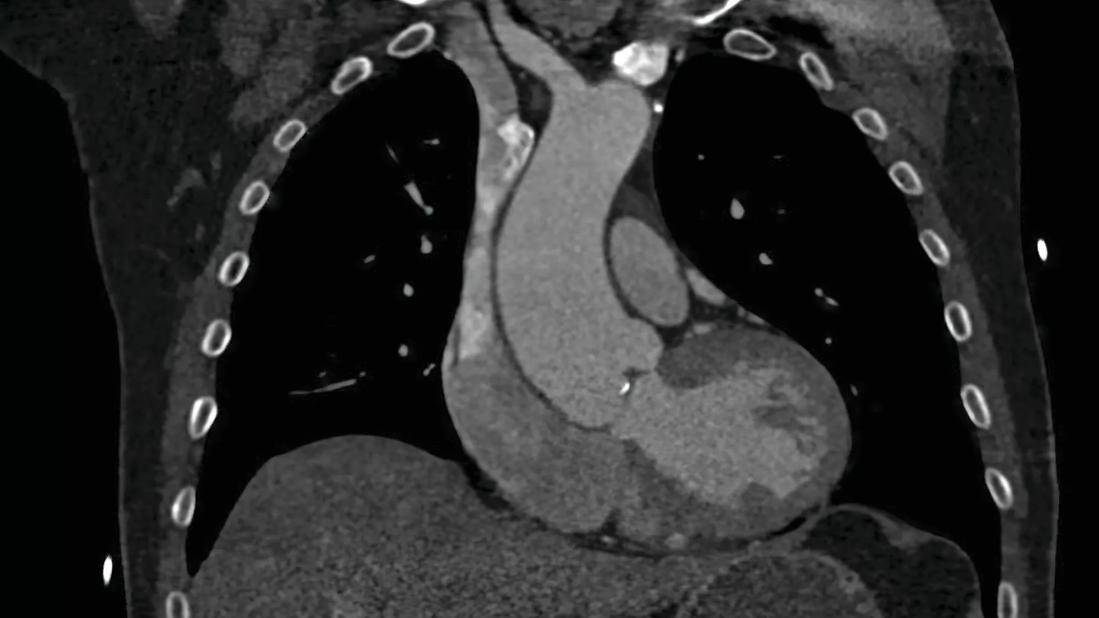

Coronal BAV aorta by CT_enlarged_CMYK

About 40 to 50% of BAV disease patients develop a dilatation of the aortic root and ascending aorta. In less than half of these cases, an aortic aneurysm is present, requiring ongoing surveillance and possible eventual repair. The aortic segments of dilatation can vary in BAV disease patients with the mid ascending region being the most common. Other phenotypes of aortic aneurysm exist, including aortic root predominant and a diffuse dilatation pattern. Rates of aortic growth vary but are unreliable to predict an upcoming aortic event. The current recommendation for elective aortic repair is an aortic diameter of 50-55 mm, with a threshold based on risk factors of family history of aortic instability or signs of rapid aortic growth.

BAV disease cases often require referral to cardiac imaging specialists who bring experience in complex valve and aortic diseases. Transthoracic echocardiography (TTE) is the standard diagnostic test when evaluating patients with a suspected aortic valve abnormality. TTE allows for accurate assessment of aortic valve anatomy and function, and the potential associated condition of aortic dilatation. Left ventricular size and function are defined by 2D and 3D volumes and ejection fraction. Transesophageal echocardiography can be used to complement TTE in cases where the diagnosis is in question or when the valve lesion requires more quantitation. In BAV disease patients with related aortic dilatation or aneurysm formation, we obtain a CT angiogram or cardiac MRI to better define aortic anatomy and baseline dimensions.